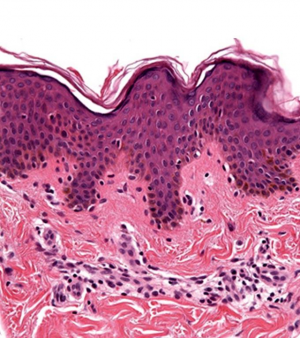

La Peau est l'organe qui recouvre l'ensemble du corps. C'est l'organe le plus vaste et le plus lourd. Son rôle est essentiel dans la protection vis-à-vis du milieu extérieur, mais elle sert également à la vie de relation par son innervation spécifique [1]

Histologie cutanée

Trois couches successives

Des annexes épidermiques localisées dans le derme